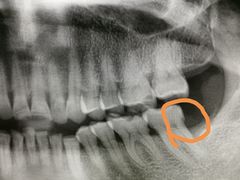

• 上海陈守平口腔诊所

• -上海陈守平口腔诊所

匿名用户 | 20-06-08

报错